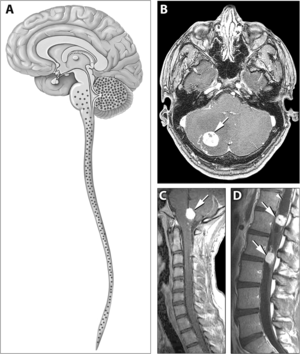

| Typical distribution of hemangioblastomas in von Hippel–Lindau disease. | |

Signs and symptoms associated with VHL disease include headaches, problems with balance and walking, dizziness, weakness of the limbs, vision problems, and high blood pressure. Conditions associated with VHL disease include angiomatosis, hemangioblastomas, pheochromocytoma, renal cell carcinoma, pancreatic cysts (pancreatic serous cystadenoma), endolymphatic sac tumor, and bilateral papillary cystadenomas of the epididymis (men) or broad ligament of the uterus (women).[5][6] Angiomatosis occurs in 37.2% of patients presenting with VHL disease and usually occurs in the retina. As a result, loss of vision is very common. However, other organs can be affected: strokes, heart attacks, and cardiovascular disease are common additional symptoms.[3] Approximately 40% of VHL disease presents with CNS hemangioblastomas and they are present in around 60-80%. Spinal hemangioblastomas are found in 13-59% of VHL disease and are specific because 80% are found in VHL disease.[7][8] Although all of these tumours are common in VHL disease, around half of cases present with only one tumour type.[8]

There is no way to reverse VHL mutations, but early recognition and treatment of specific manifestations of VHL can substantially decrease complications and improve quality of life. For this reason, individuals with VHL disease are usually screened routinely for retinal angiomas, CNS hemangioblastomas, clear-cell renal carcinomas and pheochromocytomas.[16] CNS hemangioblastomas are usually surgically removed if they are symptomatic. Photocoagulation and cryotherapy are usually used for the treatment of symptomatic retinal angiomas, although anti-angiogenic treatments may also be an option. Renal tumours may be removed by a partial nephrectomy or other techniques such as radiofrequency ablation.[7]